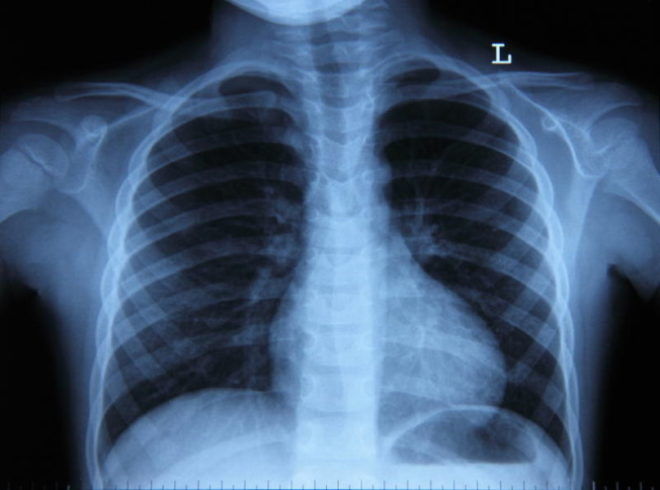

На данном фото видно, как смотрится на снимке бронхит. Кроме того, на нем отмечены некоторые его признаки.

Бронхит на снимке выявляется по таким признакам, как:

- Незначительные области инфильтрации, представляющие собой скопление в тканях легкого различных химических элементов и веществ. Также в которых имеется немалое количество жидкости.

- Увеличение толщины стенок бронхов.

- Видоизменение рисунка легких. Мелкие сосуды на нем не наблюдаются. Из-за болезни они становятся невидимыми.

- Очаговые, а также пластинчатые ателектазы.

- Нечеткие контуры.

- Расширение корня легкого. Также будет наблюдаться его расплывчатость.